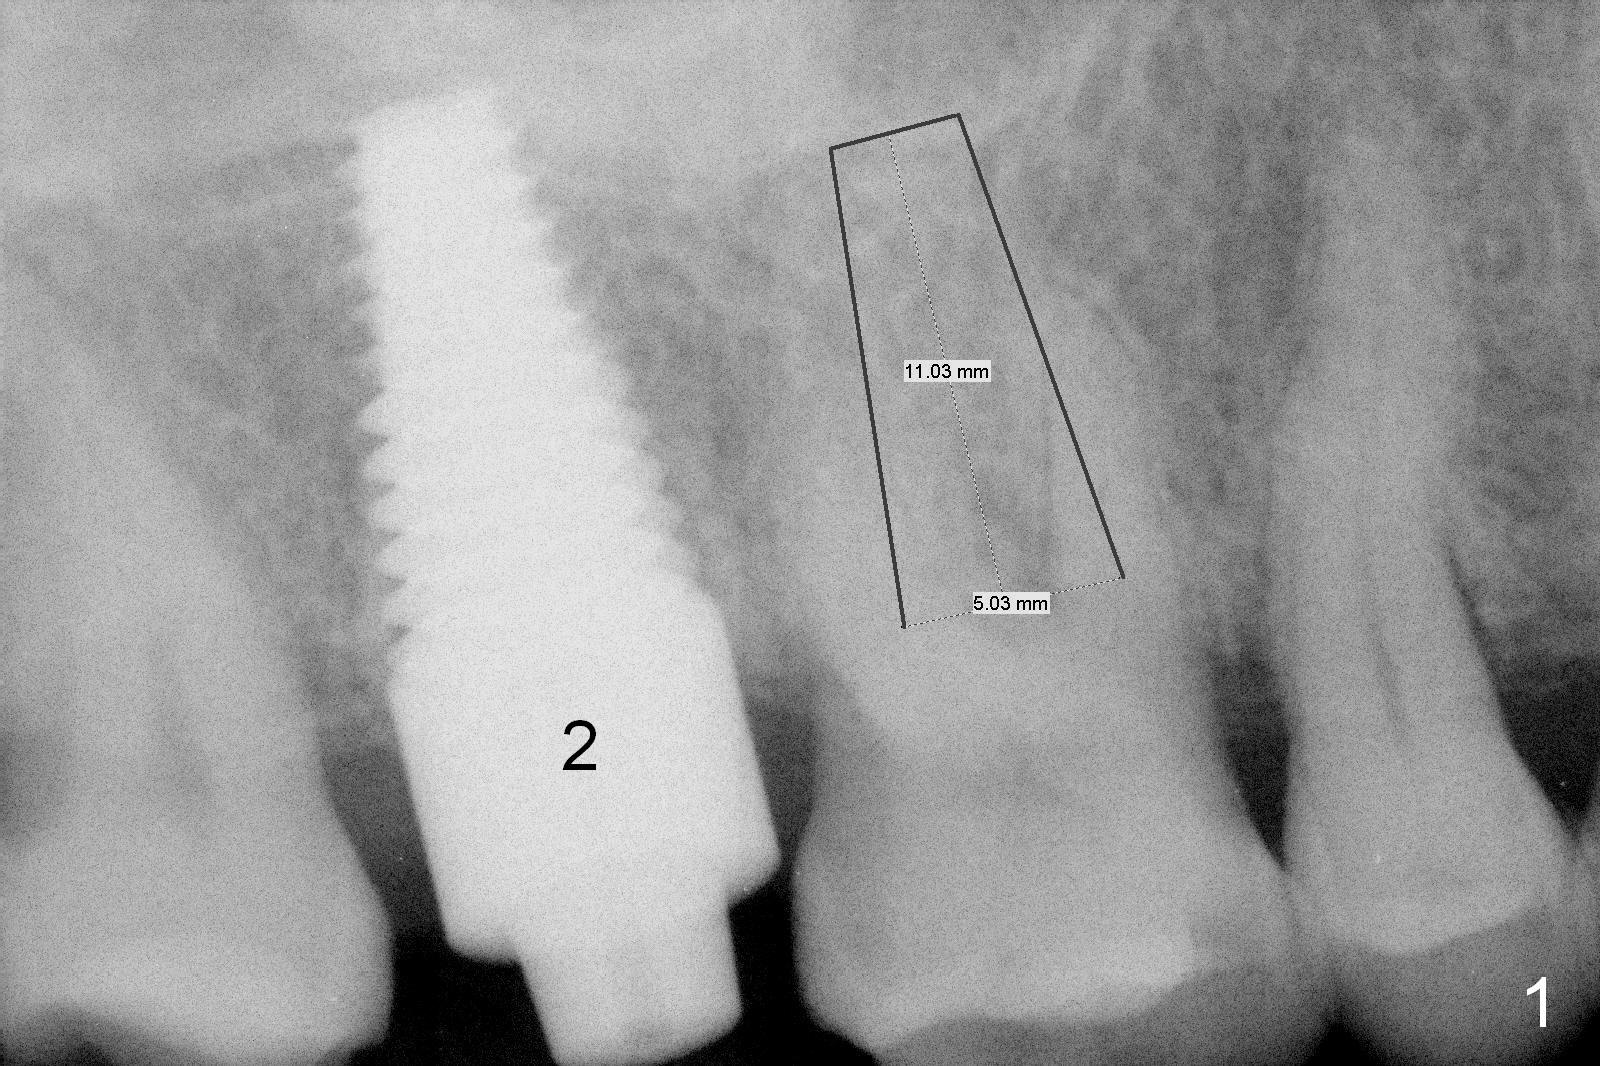

A 67-year-old woman with Parkinson disease has sign of several tooth chip.  The tooth #3 fractures mesiodistally 1 year 7 months post cementation of the crown at #2.  Take photos to show the crack line.  After extraction (Metronidazole), explore the socket to determine bone integrity.  If the septal crest is wide, use 1.6 drill (take 1st PA PRN) and Marking Bur before 4.3 mm Magic Drill.  Otherwise use sequential drills, or alternating with Magic Expander if the bone is soft.  No matter whether IBS (Fig.1) or Tatum (Fig.2) implant is placed, an immediate provisional will be fabricated so that the margin of the provisional is subgingival to prevent buccal plate collapse and bone graft leakage